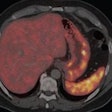

Ga-68 DOTATATE PET/CT detects neuroendocrine tumor recurrence

February 26, 2014